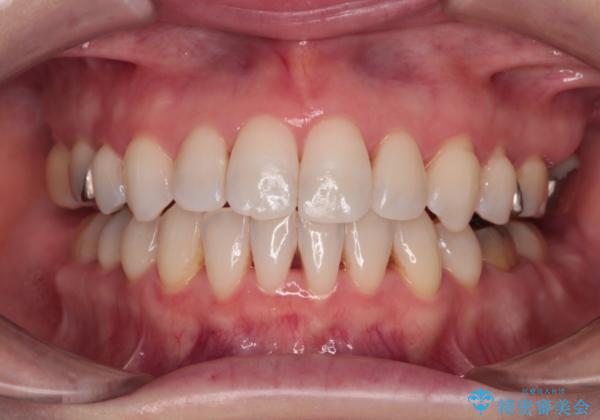

口元の突出感とデコボコがあり、上下左右の小臼歯4本を抜歯して矯正治療を行う方針としました。(右上は欠損のため計3本抜歯)

むし歯となっている歯は状態が悪く、将来的に抜歯となる可能性が高かったため、定石で抜歯させる小臼歯の代わりにむし歯となっている大臼歯を抜歯し、ワイヤー装置にて矯正治療を行うこととしました。

イレギュラーな大臼歯抜歯矯正であったため、治療期間の長期化が想定されましたが、何とか3年ちょうどで終えることができました。

今後は目立っている銀歯を中心にセラミッククラウンなどへ交換していく予定です。